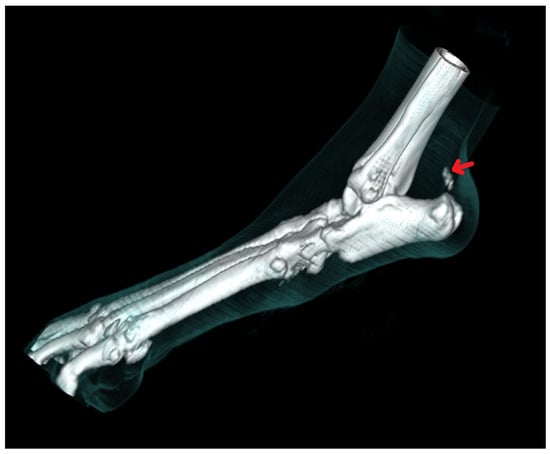

Radiography can be used for the indirect imaging of Achilles tendon injuries, but its usefulness is limited due to the superimposition of bones and poor contrast, as well as the structure visibility of soft tissues [1,40]. Radiographs can only show the foci of tendon mineralization and the swelling of adjacent soft tissue (Figure 1) [40,43]. Computed tomography (CT) is a cross-sectional imaging modality and has improved the identification of pathological lesions of the calcaneal tendon, such as enthesopathies and tendinopathies. CT provides sectional images; therefore, it eliminates the problems of superimposition correlated with conventional radiology. Achilles enthesopathy is defined as abnormality of the tendons and their attachment to the calcaneal tuber (Figure 2 and Figure 3).

Figure 1. Radiographic image of total Achilles tendon rupture. The focus of tendon mineralization (arrow) is shown.